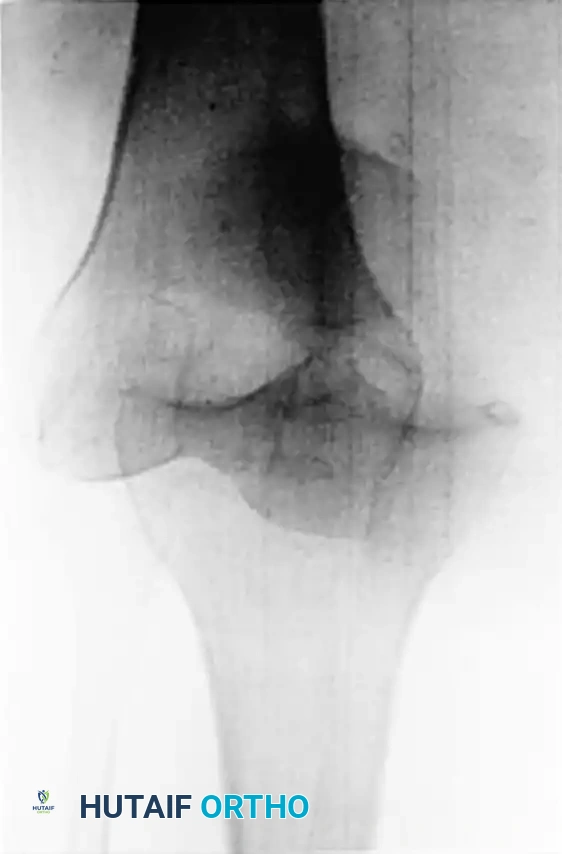

Figure 45-145: Anteroposterior (A) and Lateral (B) radiographs demonstrating an ultralow-velocity knee dislocation in a morbidly obese patient. Note the complete loss of tibiofemoral congruity.

Recent epidemiological shifts have highlighted a highly specific and dangerous subset of knee dislocations occurring in morbidly obese patients. These are termed ultralow-velocity knee dislocations. Unlike sports or motor vehicle trauma, these injuries occur during routine activities of daily living (ADLs), such as stepping off a curb, descending a single stair, or simply experiencing a mechanical fall while walking.

The biomechanical reality is that in a patient with extreme body mass, the kinetic energy generated by a simple ground-level fall is sufficient to completely rupture the multiligamentous complexes of the knee.